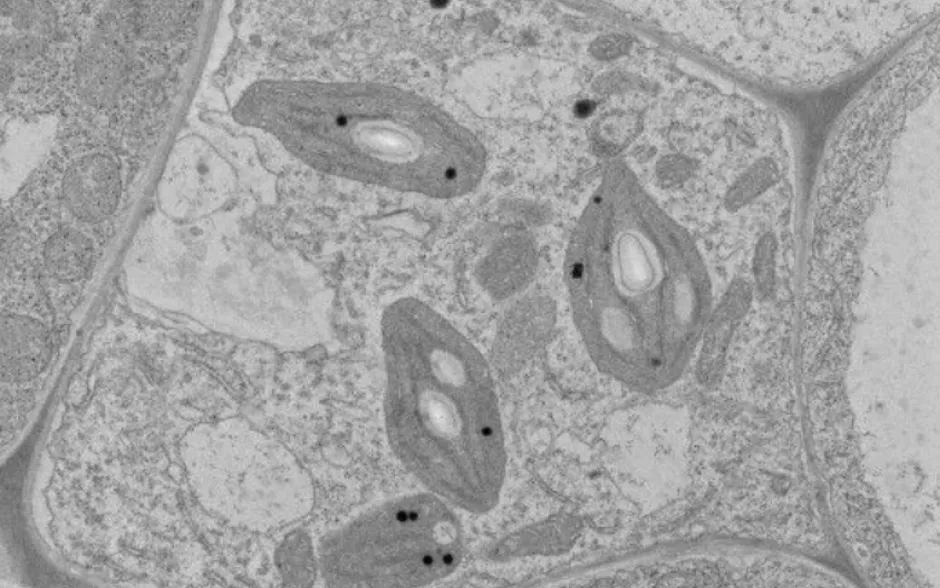

Se atienden 7 áreas, a saber: sistemas biológicos y salud, sistemas farmacológicos, espectroscopia forense, estudios arqueométricos, caracterización de alimentos y plantas, análisis de imágenes digitales y modelación computacional.

El LEMIC participa activamente en proyectos de ciencia básica y aplicada, abordando temáticas como el análisis de materiales, sistemas biológicos, farmacología, conservación del patrimonio y modelación computacional. También promueve la colaboración con instituciones nacionales e internacionales para el desarrollo de investigaciones de alto impacto.